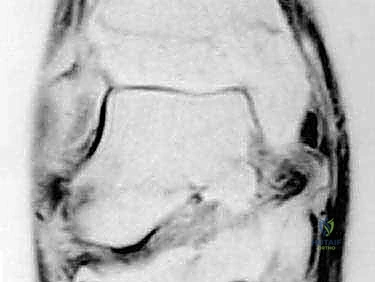

3. التصوير بالرنين المغناطيسي (MRI)

يُعد الرنين المغناطيسي المعيار الذهبي لتقييم الأنسجة الرخوة. يسمح للدكتور هطيف برؤية مدى تمزق رباط الدالية (جزئي أم كلي)، وتقييم حالة وتر الظنبوب الخلفي، واكتشاف أي إصابات مصاحبة في الغضاريف المفصلية (Osteochondral Lesions) التي قد تتطلب تدخلاً بالمنظار.